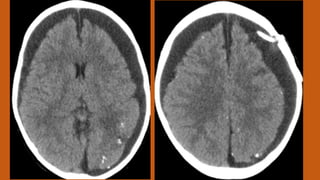

Este documento presenta el caso de un niño de 3 años que sufrió episodios de paresia y alteraciones neurológicas. Exámenes revelaron la presencia de un higroma cerebral que fue drenado. A pesar de una mejoría inicial, el niño continuó presentando síntomas neurológicos intermitentes. Exámenes posteriores identificaron una rara vasculopatía que afecta vasos cerebrales y otros órganos, con un pronóstico grave.